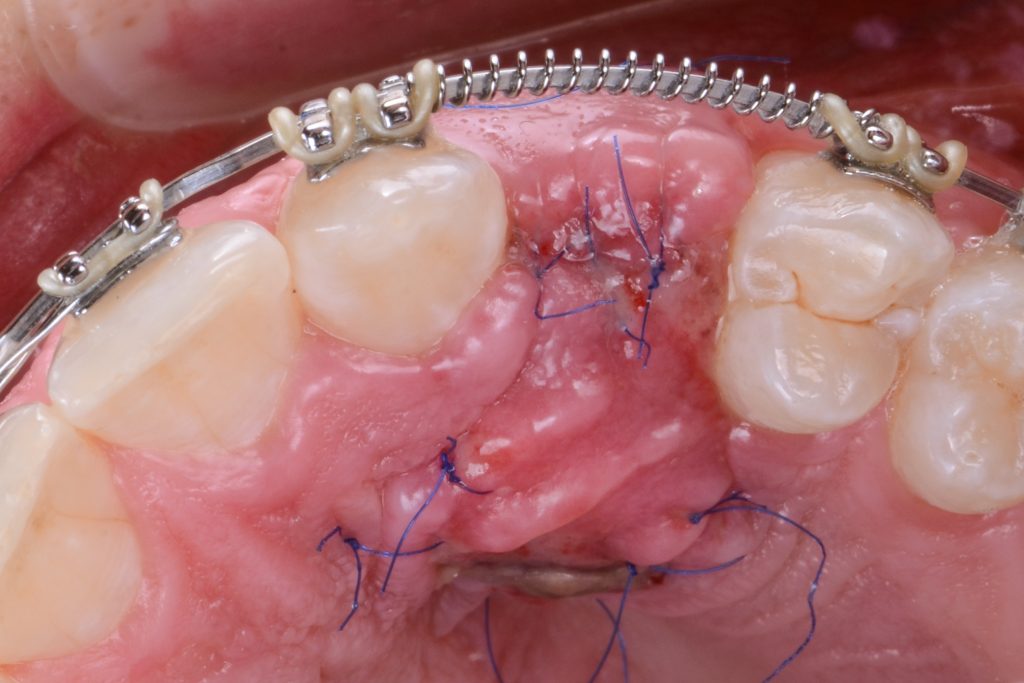

the sliding island flap secured with 6/0 stitches

the situation 10 days after the surgery